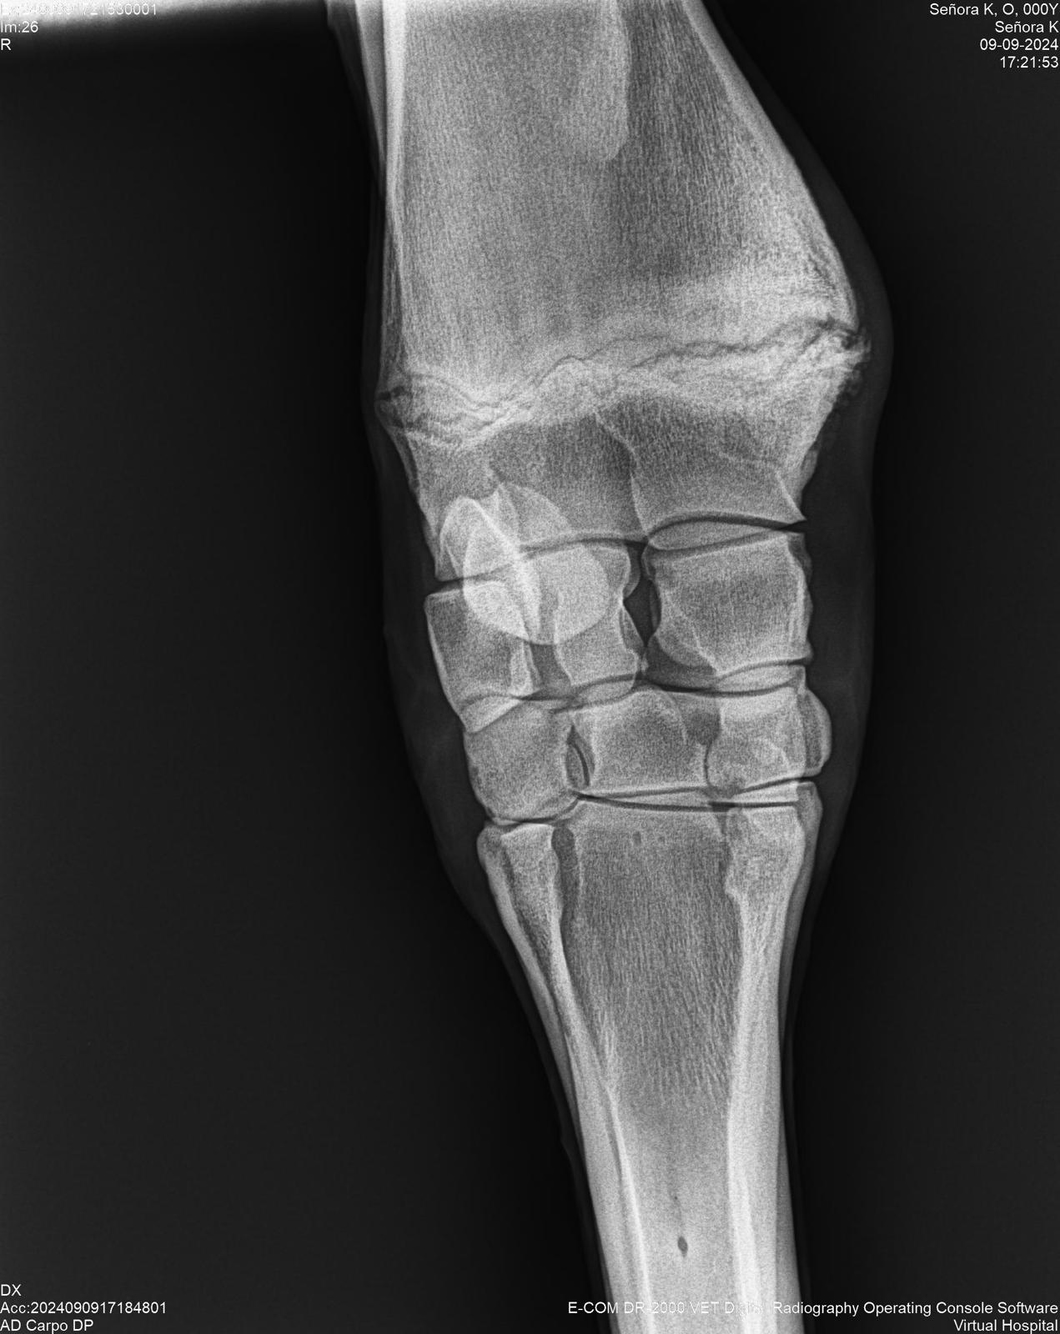

LOTE 44, SEÑORA K

Identificador: #291147-

Generacion 2022